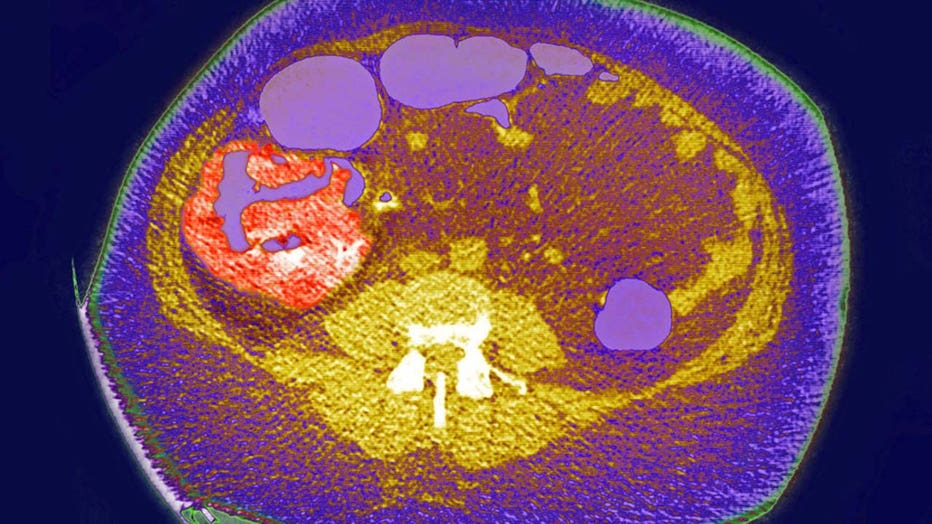

FILE - Colon cancer, tumor on the caecum and ileocolic valve, visualization on a radial CT scan.